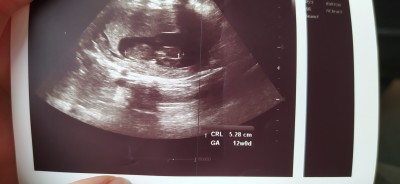

13 haftalık ultrason görüntüsü sizce kız mı erkek mi tahmini olan yazabilir misiniz

Başka ultrason resmi varmi canim

Kıza benziyor dedi doktor bildiniz☺️

Göstermedi dedi bacak arasıni kapatmış

Çikolata yedim meyve suyu içtim ama malesef hemen arkasını döndü